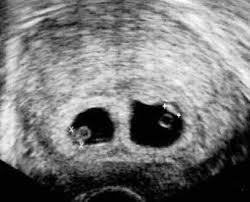

Hamileliklerin bir kısmı çok erken dönemde birden fazla bebek içerecek şekilde yani ikiz veya üçüz olarak başlamakta ancak daha sonraki kontrollerde bu bebeklerden ya da daha doğru bir deyişle gebelik keselerinden biri hiçbir iz bırakmadan kaybolmaktadır.Bu durum "kaybolan ikiz" (vanishing twin) sendromu olarak adlandırılır. İkiz gebeliklerin % 20’ sinde fetuslardan biri kendiliğinden kaybolmaktadır. Üçüzlerde ve dördüzlerde bu, daha fazla olmaktadır. Fetus ilk üç ayda kaybolduğunda vajinal kanama olabilse de, kalan fetus veya fetuslar genellikle normal gelişimlerini devam ettirmektedirler.

Ultrasonun yaygın kullanıma girmesi ile hamilelikler 5-6 hafta gibi son derece erken sayılabilecek bir dönemde saptanabilmekte, hatta gebeliğin gidişatı ile ilgili fikir elde edilebilmektedir. Ultrasonun bu yaygın kullanımı çok ilgi çekici bir durumun varlığının farkına varılmasına aracı olmuştur. Ayrı yumurta ikizlerinin yaklaşık % 10’ u, aynı yumurta ikizlerinin yaklaşık % 80’ i beşinci haftadan sonra görülebilmektedir. 6-8 haftadan sonra ultrason fetusların sayısına dair kesin değerlendirmeyi sağlayabilmektedir.Çoğul Gebelikte Risk Faktörleri